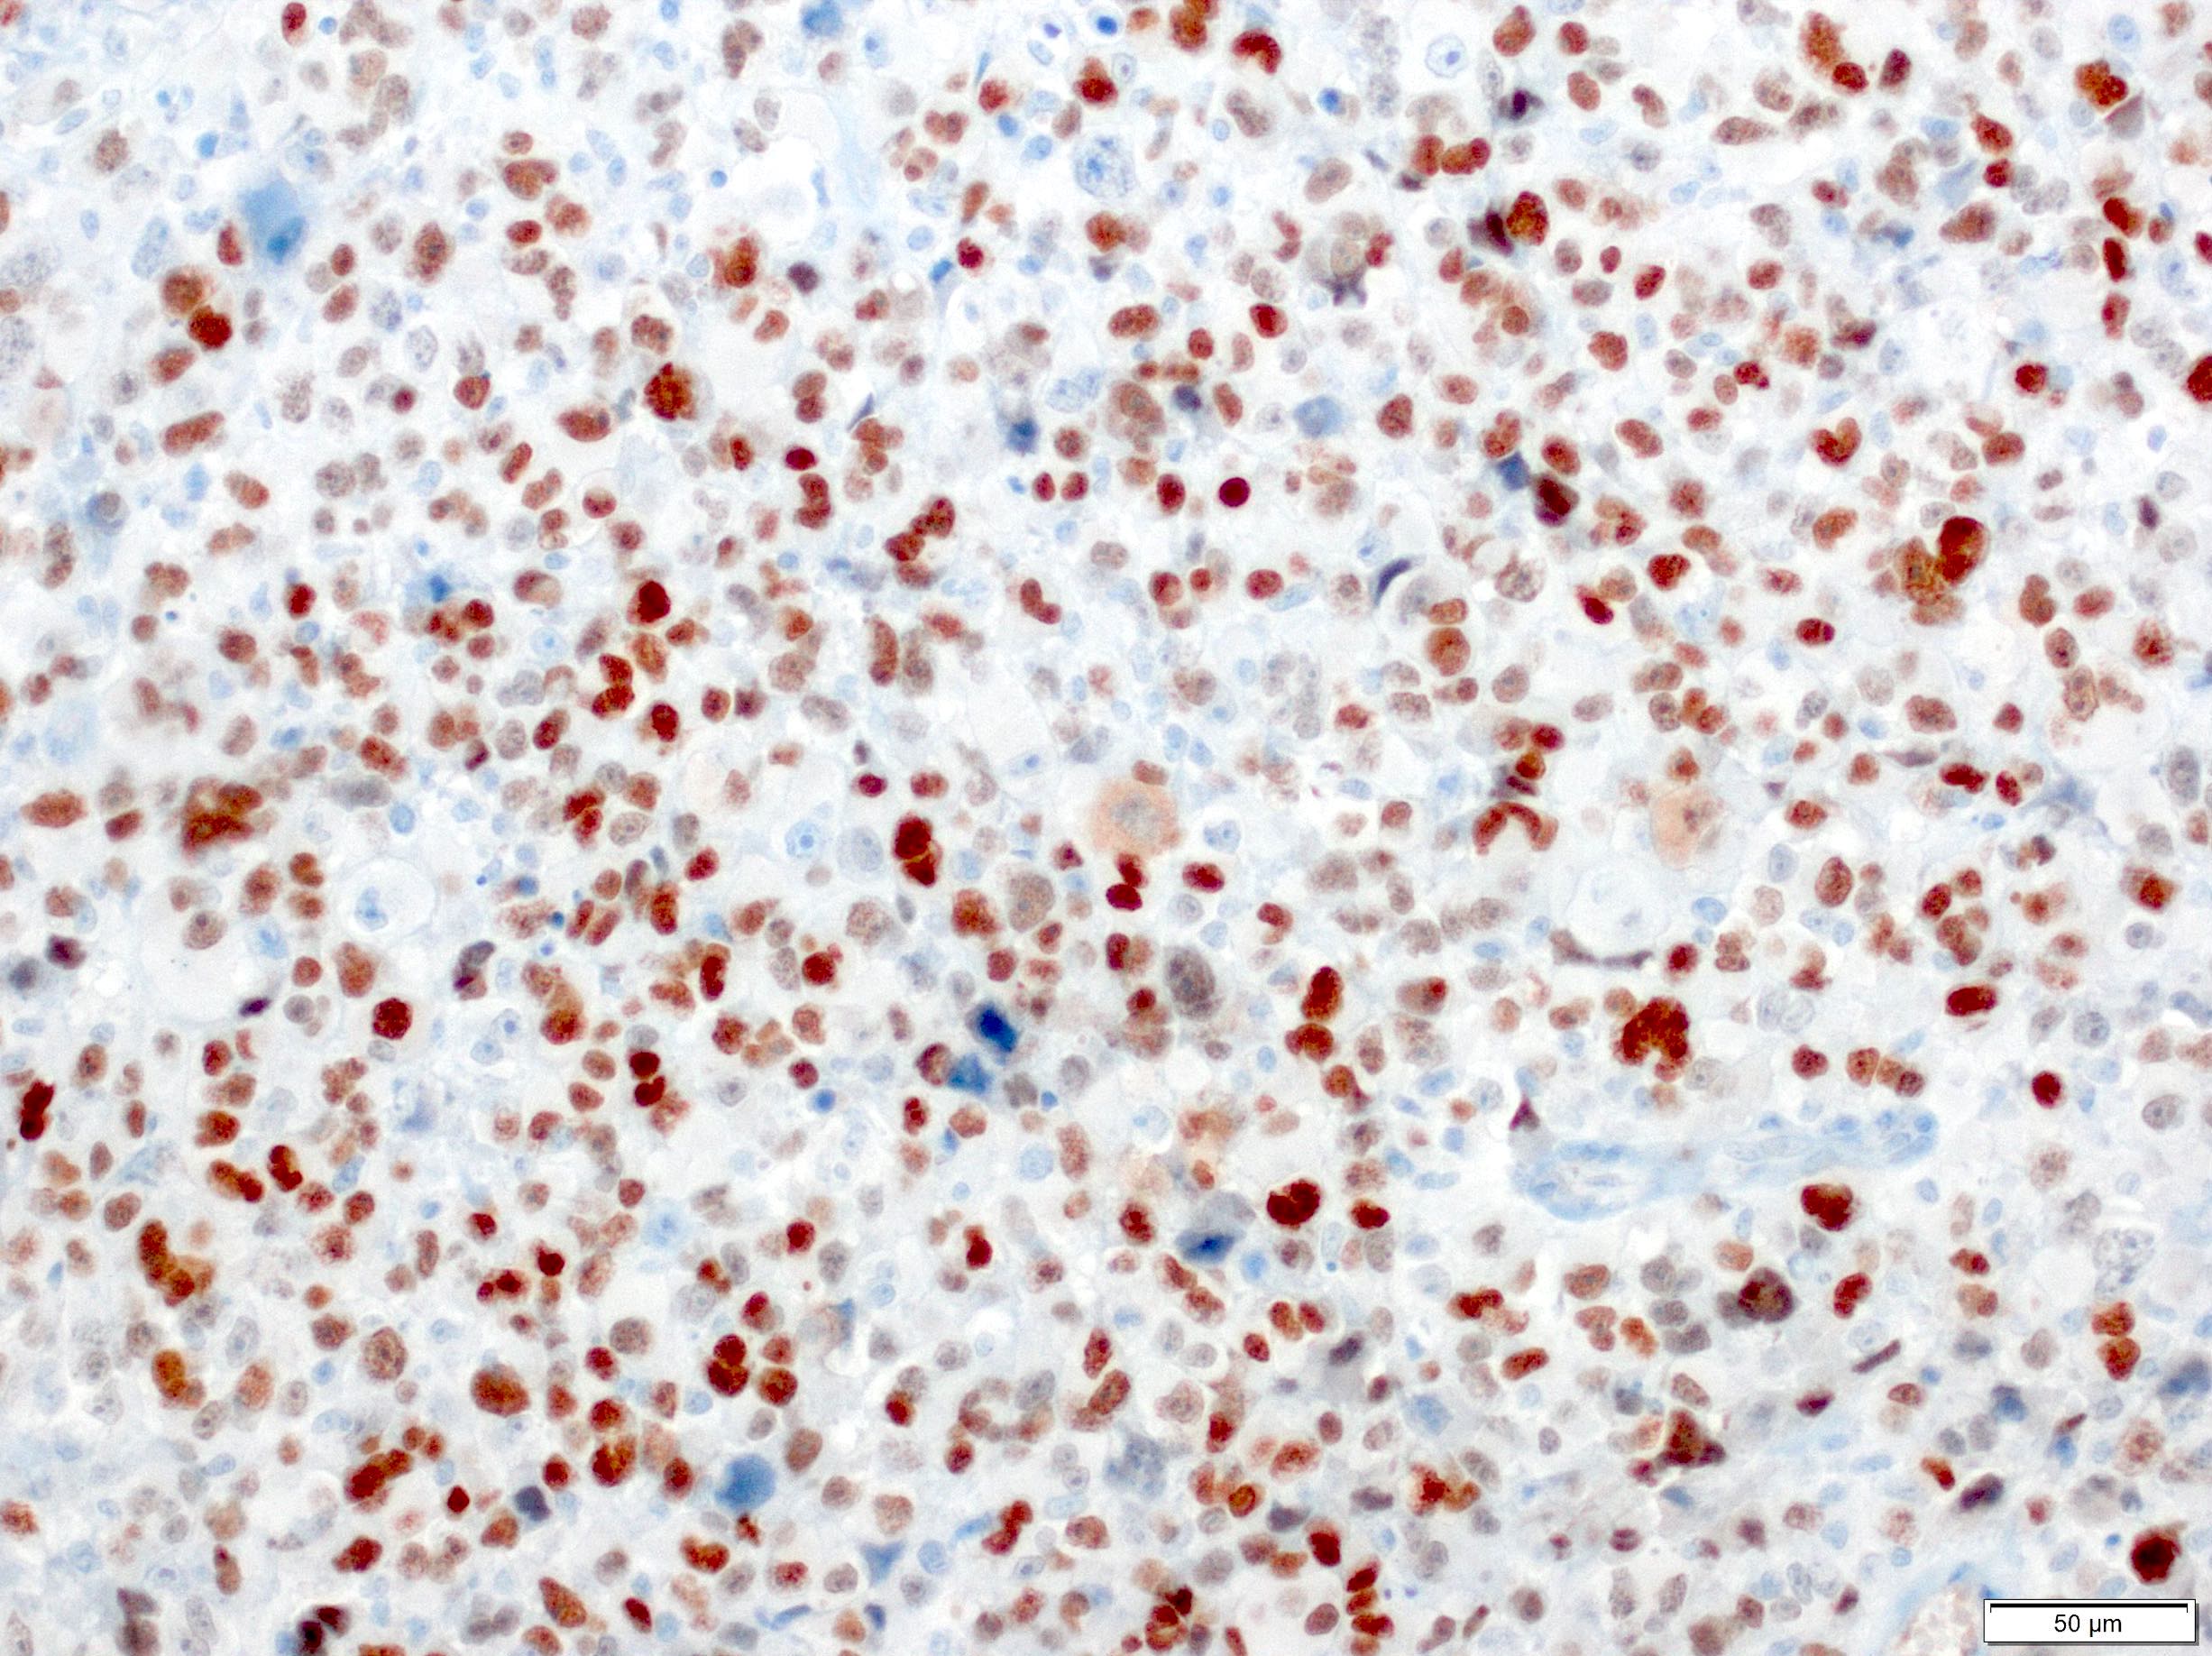

- High grade sarcoma composed of atypical cells that display skeletal muscle differentiation, confirmed with immunohistochemistry for myogenin or myoD1

- Pleomorphic cells with brightly eosinophilic cytoplasm (Mod Pathol 2001;14:595)

- Skeletal muscle differentiation as confirmed by desmin, myogenin or MyoD1 (Ann Diagn Pathol 2018;36:50)

- Sheets of large, atypical and frequently multinucleated polygonal, spindled or rhabdoid eosinophilic cells (Am J Surg Pathol 2009;33:1850)

- Cross striations are seldom detected

Positive stains

- Expresses desmin, MyoD1, skeletal muscle (fast) myosin and myogenin (Mod Pathol 2001;14:595)